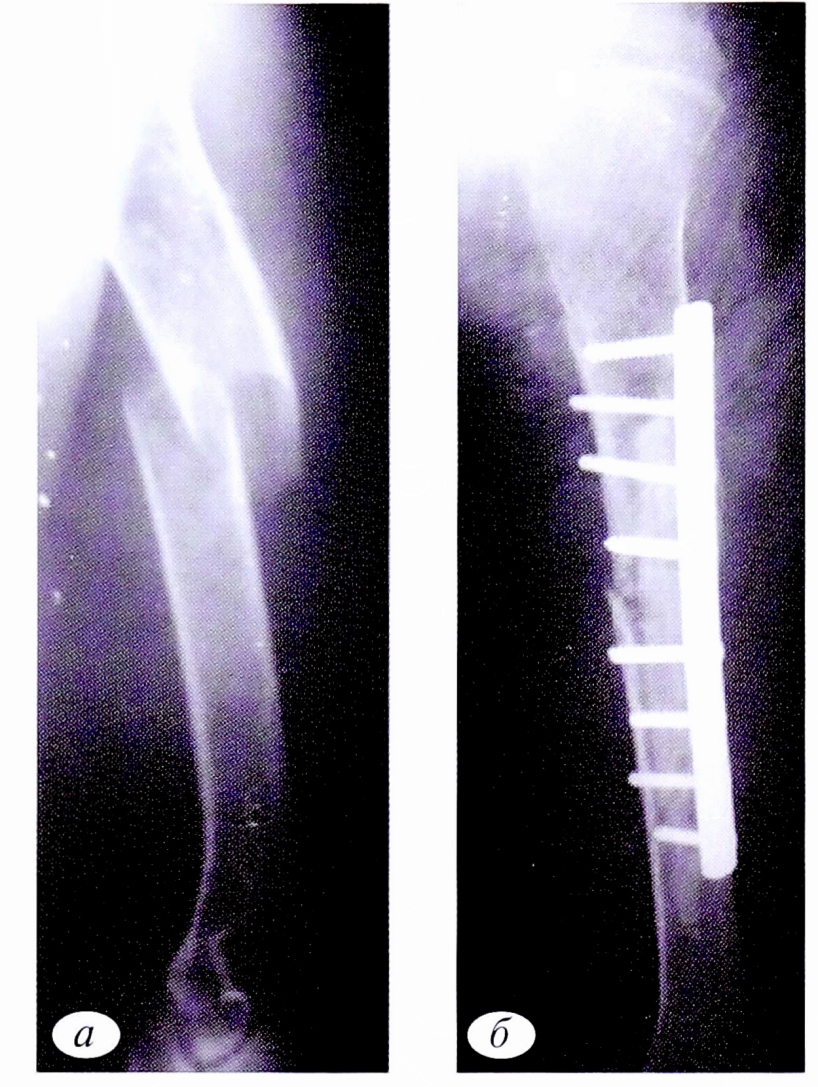

При болезни Олье основные клинические проявления (деформация и укорочение пораженных сегментов скелета) возникают достаточно рано — в возрасте от 2 до 10 лет. Несмотря на то что заболевание диагностировалось в раннем возрасте и больные получали соответствующее оперативное лечение, эта категория пациентов оставалась в зоне риска возникновения патологических переломов, которые имели место в 6 случаях: 4 без смещения,2 со смещением. При лечении пациентов проводилась краевая резекция кости с удалением патологического очага в пределах здоровой ткани и последующим замещением дефекта трансплантатами. Остеосинтез перелома выполнялся металлоконструкцией (рис. 8).

Рис. 8. Пациент И.,15 лет. Диагноз: патологический перелом средней трети левой плечевой кости на фоне болезни Олье. Рентгенограммы левой плечевой кости: а — до операции; б — после операции: открытая репозиция, краевая резекция нижней и средней третей левой плечевой кости, аллопластика, металлоостеосинтез.

Fig. 8. Patient /.,15 years old. Diagnosis: pathological fracture of the middle third of the left humerus due to Ollier disease. a — radiographs of the left humerus before surgery; б — radiographs of the left humerus after surgery: open reduction, marginal resection of the lower and middle third of the left humerus, alloplasty, metallosteosynthesis.